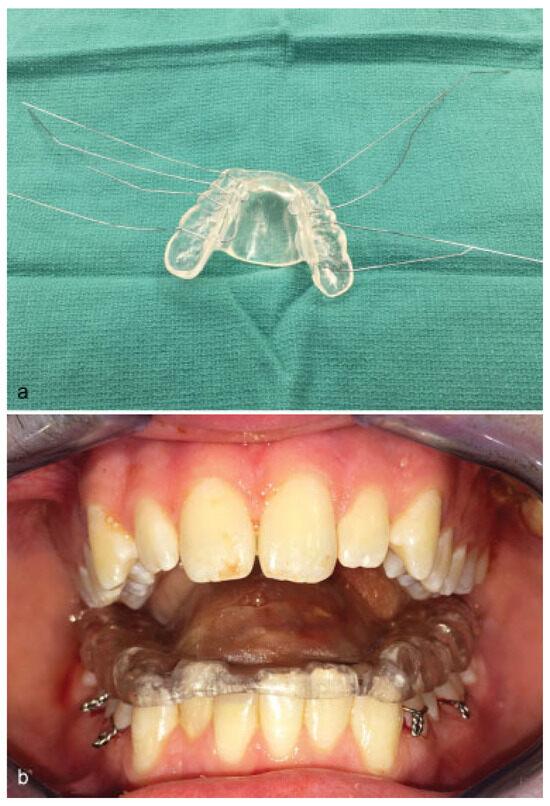

To clarify the conflicting recommendations for care of blowout fracture (BOF), a prospective randomized study is required. Here, we present a prospective randomized pilot study on BOF. This article aimed to evaluate which computed tomography (CT) fin...